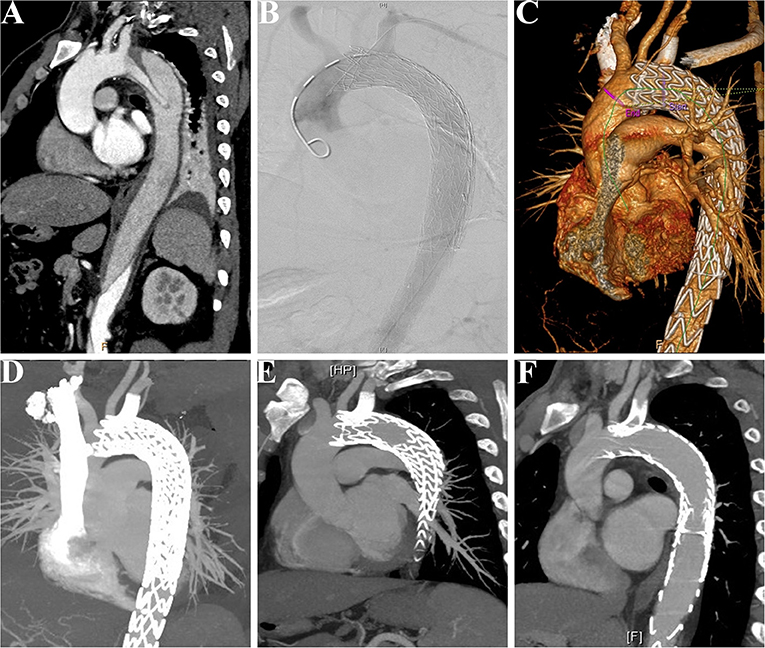

During the median follow-up duration of 38.9 (range, 18.8–44.2) months, there was one (3.8%) case of retrograde type A aortic dissection (AAD) at 3 months after TEVAR. The patient then received the total arch replacement and survived until the last follow-up. From the investigation of follow-up CTA, all the branch stents were patent (Figure 5) and had no other stent graft-related complications (Table 3). There was no all-cause mortality during the follow-up.

Figure 5. Patency of the LSCA was followed-up in a patient receiving the MCPF technique. (A) Preoperative CTA showed that a patient suffered from thoracic aortic dissection, which involved the LSCA. (B) Intraoperative aortogram demonstrated that the LSCA was revascularized and false lumen was excluded. (C) Before discharge, CTA was conducted to confirm the patency of the LSCA and exclusion of false lumen. (D) CTA at follow-up of 6 months. (E) CTA at follow-up of 12 months. (F) CTA at follow-up of 24 months. LSCA, left subclavian artery; MCPF, mini-cross prefenestration; CTA, CT angiography.